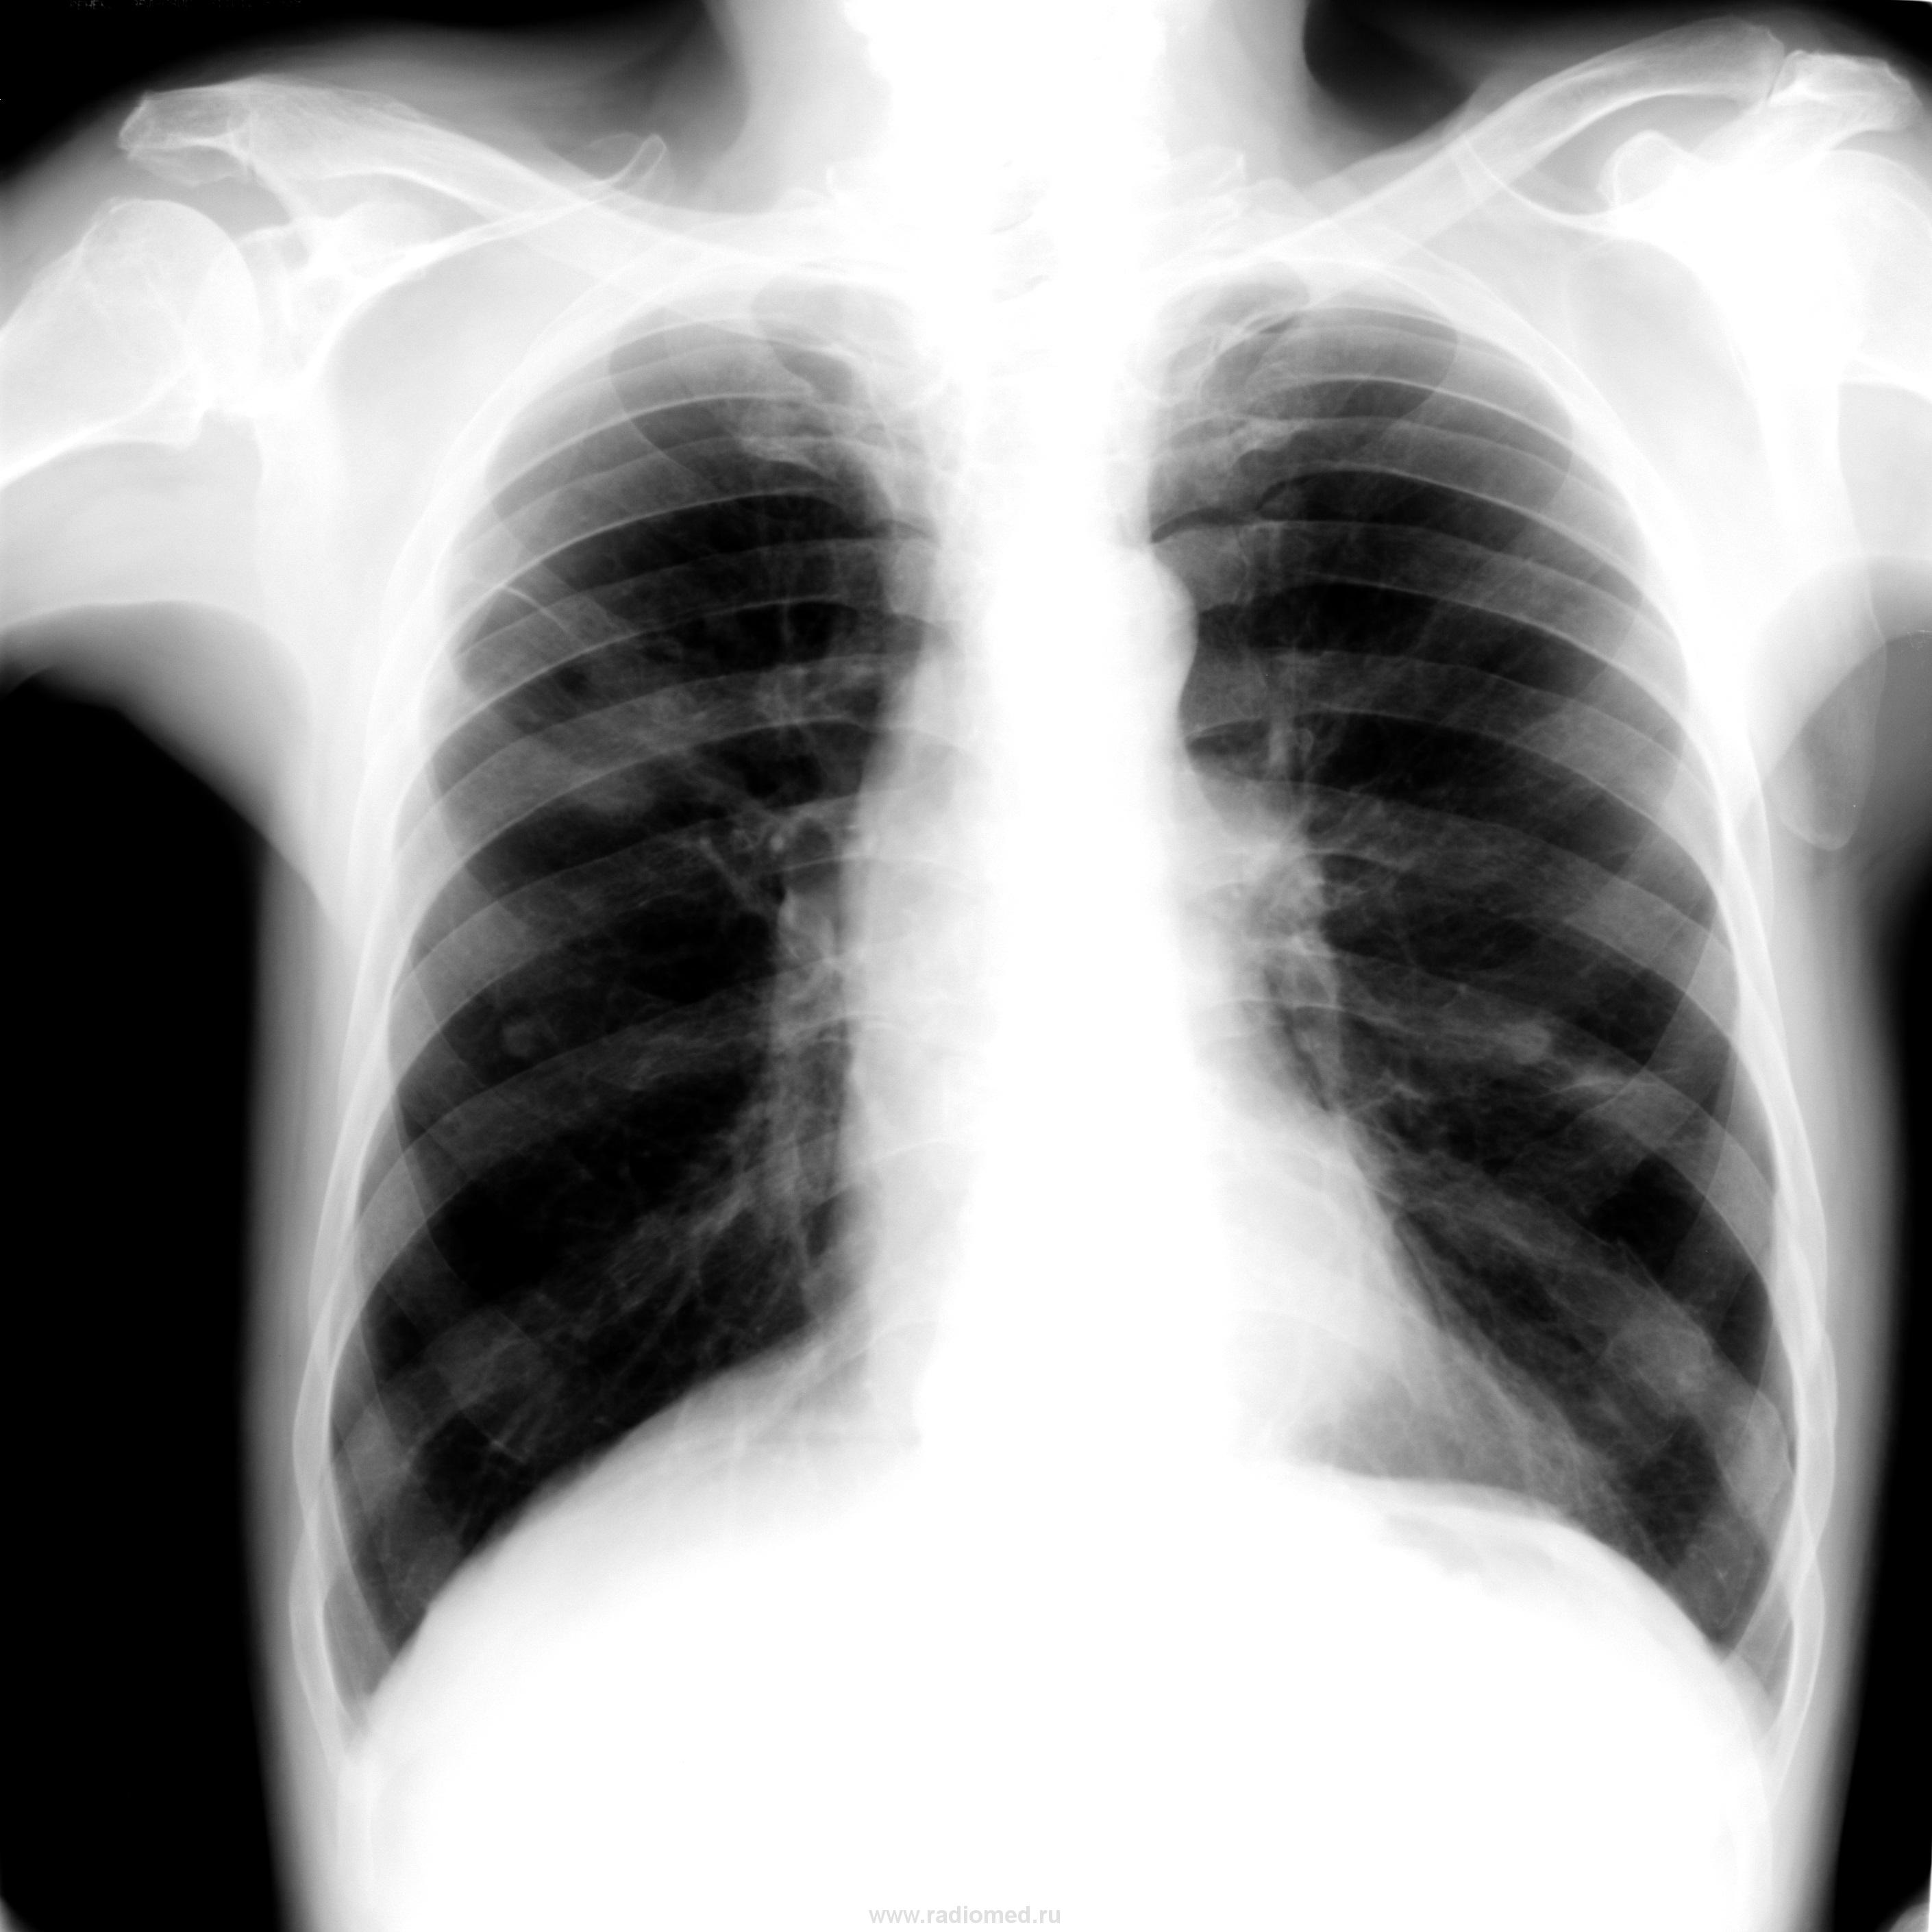

Я увидел 4 патологические тени,выпот справа и старый перелом ребра слева.Сейчас больным занялся онколог.Дообследование обещает быть всеобъемлющим,отпраляется больной в институт Герцена.

Да,очень интересные легкие,особенно верхняя доля,ее объем.И что за междопевая за 3 ребром?(если это междолевая)Чуть бы информации,и качества.Пока за онко.

Метастазы наверное, в верхней доле справа несколько странных теней. Симметричные тени в средних отделах легочных полей это соски или нет? Не пойму никак

На мой взгляд, кальцинаты в верхней доле справа, более крупные и тоже плотные тени с обеих сторон, плевро-костальные наложения спереди (думаю, что это не осумкованный выпот), некоторая «плакучесть» корней – всё это с большой долей вероятности позволяет предположить фиброзные изменения и этим объяснить признаки гиповентиляции верхней доли справа. Из свежего - мнение об инфильтративном твс в S2 справа. Хотя в S2 могут быть и фиброзно-кавернозные изменения без свежего процесса, учитывая, что клиники нет.

Считаю, что показано КТ. На линейке затруднился бы с «определением локализации цели срезов».

Также, на мой взгляд, здесь есть очаговые тени за первым ребром справа.

Да, здесь онкология, субсегментарный ателектаз и боюсь, что уже задействованы и лимфоузлы. В язычках-дисковидные ателектазы( или фиброзные изменения). В любом случае прямое показание для КТ и ФБС. Мелкоклеточный рак так себя ведет.И аденокарцинома, толко вид у нее немножко другой. Предвижу издевки:" С ума что-ли сошла,- о виде опухоли говорить по обзору?" Нет, не сошла,но имеете полное право так думать.

Периферический C-r в S3 справа.

Предполагаю, что в легких не один очаг (узелок; узел); возможно mts процесс. Показано КТ исследование (конечно, если есть возможность!).